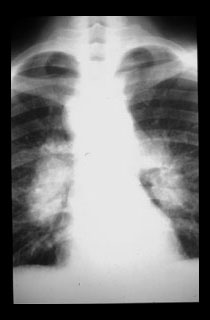

Bilateral symmetric hilar and right paratracheal mediastinal adenopathy, as in this patient, is the most common pattern of lymphadenopathy in sarcoidosis. |

At the time of diagnosis there are marked enlarged hilar and mediastinal lymph nodes. |

Two years later the lymph nodes are smaller and there is parenchymal lung disease.